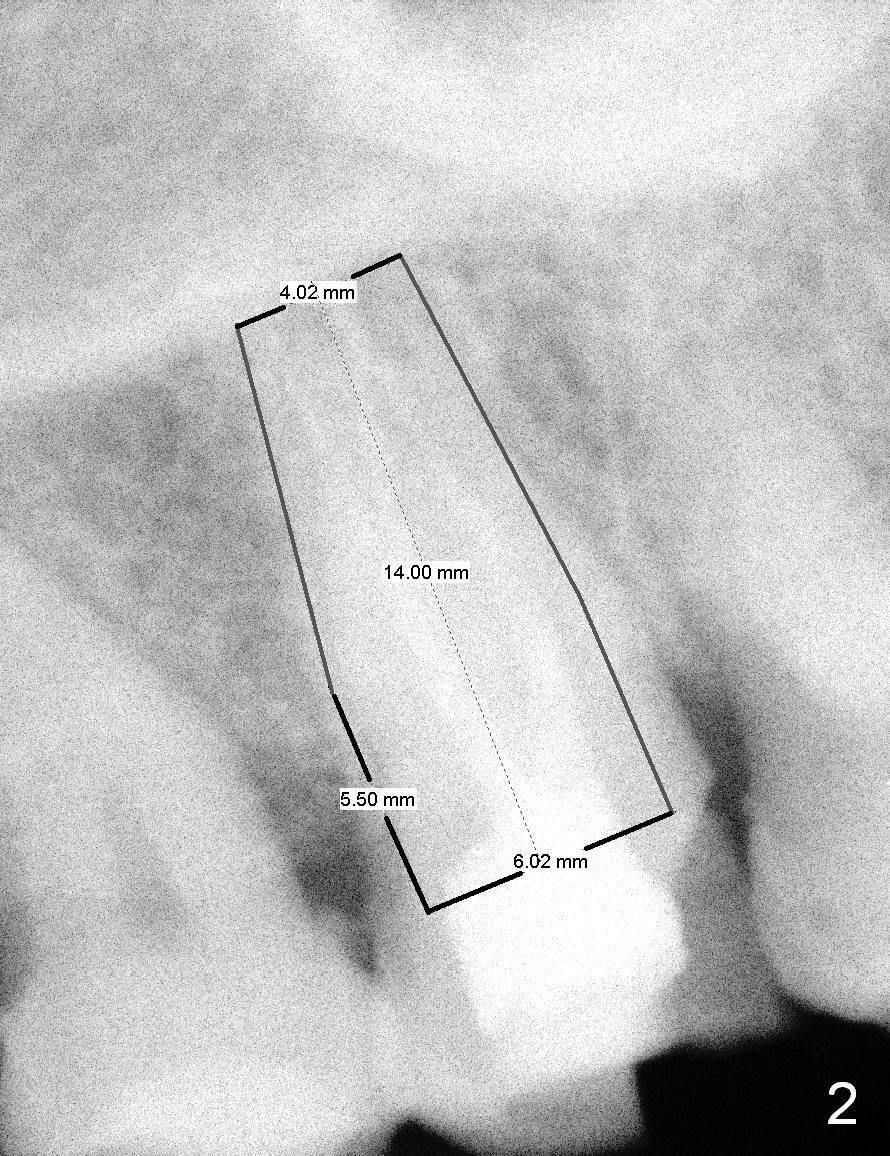

A 65-year-old lady is at early stage of Parkinson's disease and appears to be a bruxer. There are multiple chipped teeth, including #2 (Fig.1,4 *). She chooses implant over RCT retreat. A tissue-level implant (Fig.2) matches the root shape of the affected tooth better than a bone-level one (Fig.3), because of taper. The buccopalatal and mesiodistal dimensions of the extraction socket are 11 and 8 mm, respectively (Fig.5,7).